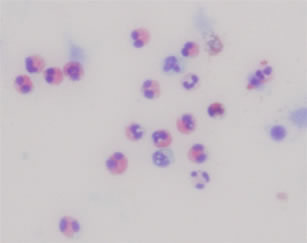

夜間や早朝に悪化し、日中に軽快する咳や痰や喘鳴があるような典型例では診断は容易ですが、咳だけが3週間以上も続く場合は見逃される場合もあり注意が必要です。当科では、患者さんの症状のほかに、呼吸機能検査による可逆性検査や「喀痰中の好酸球の増加」(図3)および好酸球性気道炎症の程度と良い相関関係を示す「呼気中の一酸化窒素(NO)濃度」(図4)の測定などの客観的検査を組み合わせて正確な診断を行っております。

図3. 誘発喀痰中の好酸球 好酸球:赤く染まった細胞